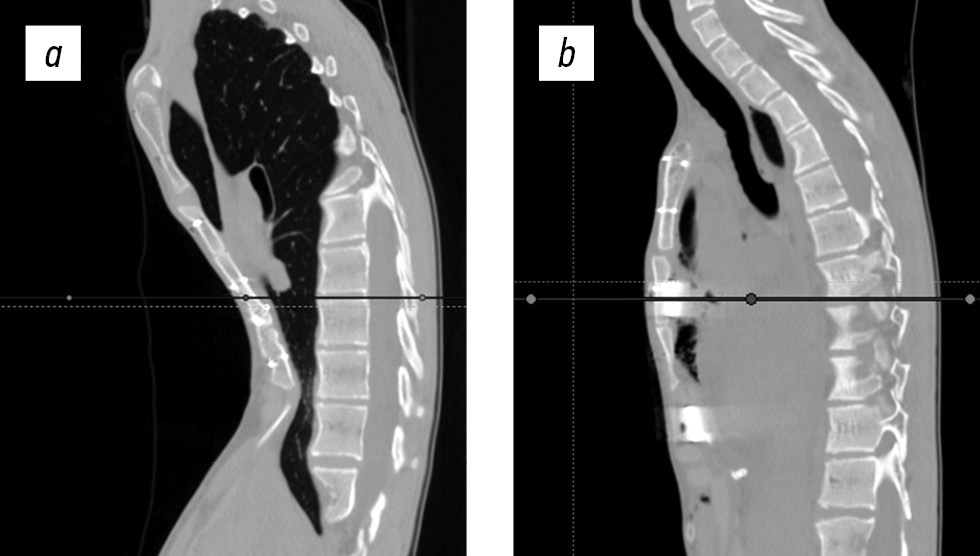

Рентгенография грудной клетки: не выявлено особенностей по сравнению с данными компьютерной томографии, определена деформация позвоночника с основной левосторонней поясничной дугой с вершиной на II позвонке до 78° и грудным правосторонним противоискривлением до 34° в положении стоя (рис. 1).

Рис. 1. Рентгенография позвоночника пациента на протяжении в прямой проекции, в положении стоя: поясничный левосторонний сколиоз с протяженным грудным противоискривлением; серкляжный проволочный шов грудины после продольной стернотомии, опорное полукольцо митрального клапана.